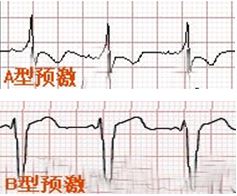

3、Δ波

Δ波又叫预激波,关键在“预”字上,如下图所示,有一个预先的电冲动传导给心室,激动部分心室(下图中左侧橙色表示的部分心肌),但心室还没有完全激动起来,如果激动起来就成了早搏了,没有完全激动的心室在心电图上的表现就是在QRS波群前面出现了一个小斜坡(下图右侧橙色小三角上的斜坡)。

如果delta波与R波都是向上的,表示预先的电冲动来自左侧旁路,也就是A型预激波,反之则为右侧旁路,即B型预激波。这点判断主要是看V1导联,当然要结合其他导联。

图9

图10